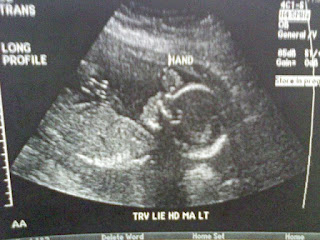

As some of you may know, Leeland was diagnosed with a genetic disorder called Nuerofibromatosis (NF1) at 6 months. At the time he presented with 1 side effect (at 6 months) he is now 3 and between the time when he was first diagnosed and now he has shown 6 new signs of NF1. Here’s a little info on Nuerofibromatosis. Nuerofibromatosis is caused by genetic defects that either are passed on by a parent or occur spontaneously at conception. The specific genes involved depends on the type of nuerofibromatosis. In this case neither my husband nor I carry the gene. And Leeland has NF1 NF1 gene is located on Chromosome 17 this gene produces a protein called nuerofibromin, that helps regulate cell growth. The mutated gene causes a loss of nuerofibromin, which allows cells to grow uncontrolled. What is NF1? It’s a genetic disorder that causes tumors to grow on nerve tissue. —Brain —Spine —Nerves Tumors are usually benign, but can sometimes become ...